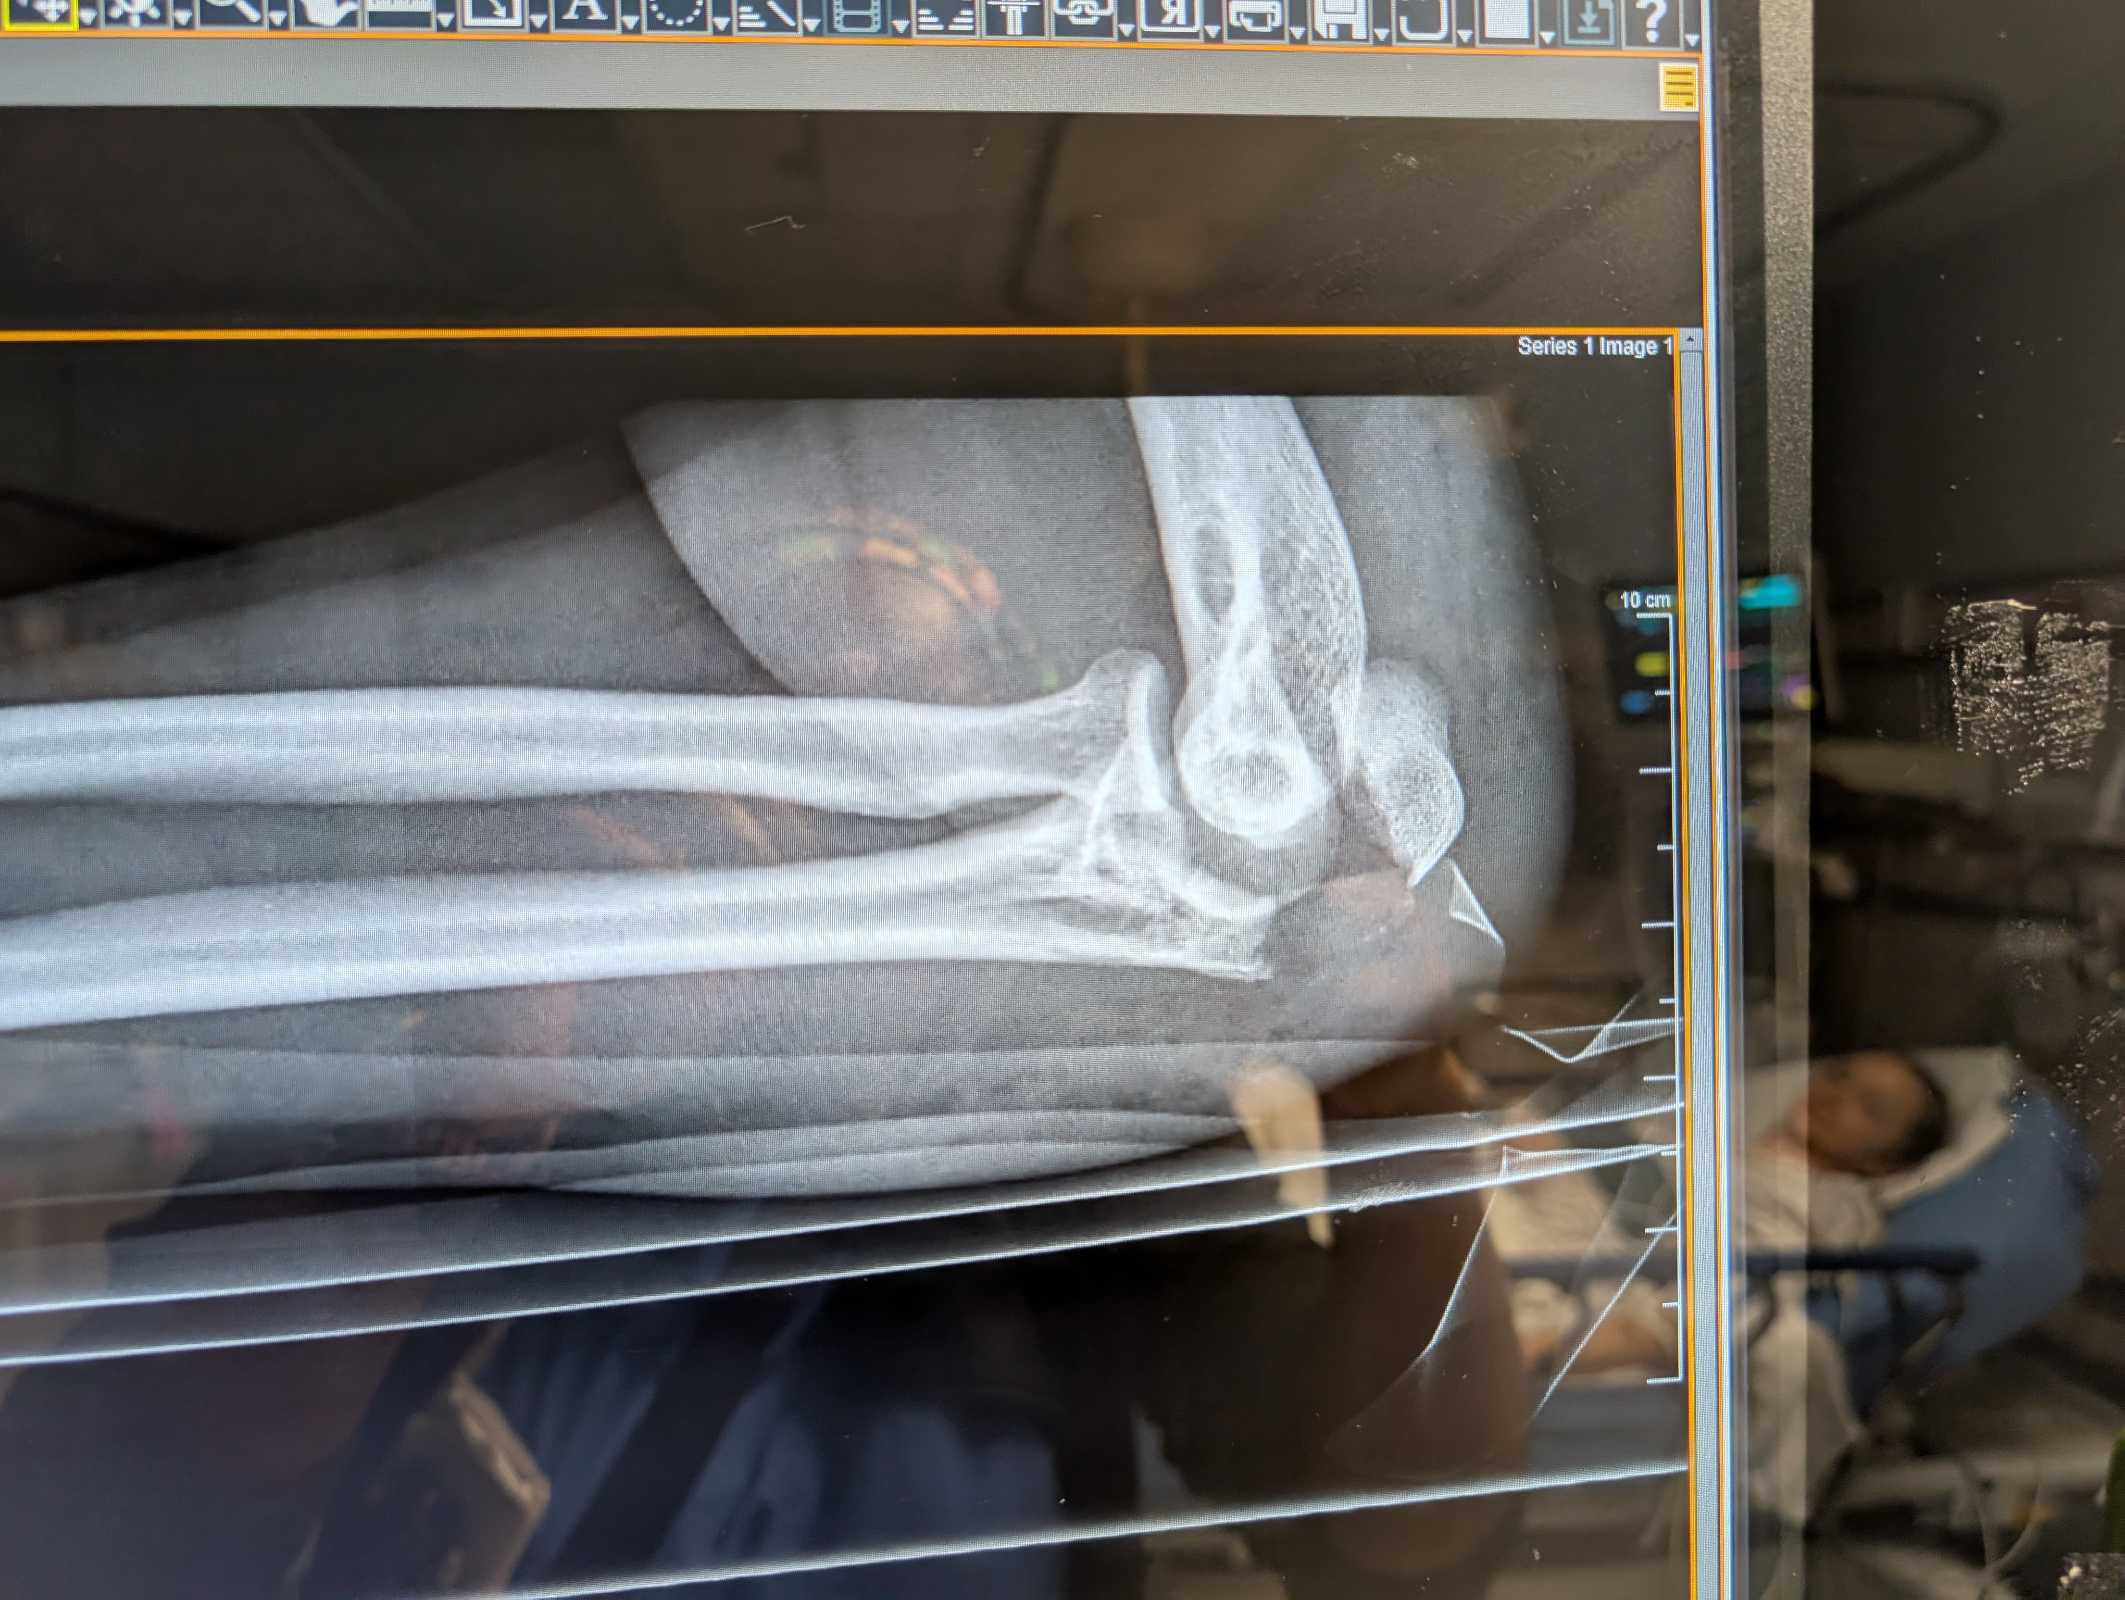

My shattered elbow